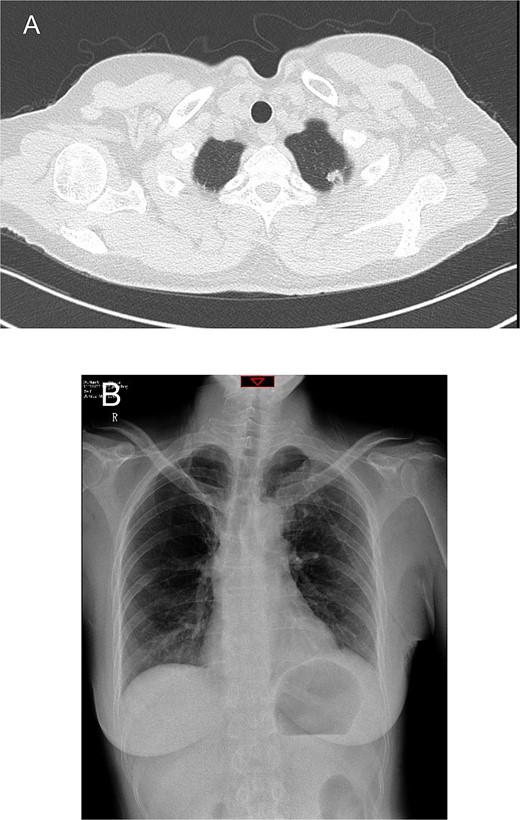

On the third postoperative day, the patient experienced sudden, severe left shoulder and back pain while semi-recumbent. She appeared distressed, pale, and diaphoretic, with a blood pressure of 79/51 mmHg and a heart rate of 116 bpm. Rapid fluid resuscitation and dopamine infusion were initiated. An emergent chest CT revealed a large hemothorax, suggesting postoperative bleeding (Fig. 2A).

Preoperative chest computed tomography and intraoperative findings on postoperative day 3. (A) Computed tomography shows a large amount of fluid in the left pleural cavity, indicative of postoperative hemorrhage. (B) A protruding staple (black arrow) is observed at the resection margin of the left upper lung, near the site of chest wall bleeding. (C) During surgery, we attempted to reproduce the position that caused the bleeding.

Immediate reoperation was performed. Upon re-entering the chest through the original incision, a substantial amount of blood clots were found. Active arterial bleeding was observed from a small vessel at the second intercostal space on the posterior chest wall, presuming to be the left second intercostal artery (Fig. 3). Hemostasis was achieved using electrocautery. Additionally, a protruding staple at the left upper lobe resection margin was noted, likely causing abrasion against the chest wall (Fig. 2B and C). The staple was removed, then the lung tissue was sutured using 4-0 non-absorbable monofilament. Hemostatic agents were applied to the bleeding sites. The total blood loss, including intraoperative and chest cavity blood, was ~2800 ml.